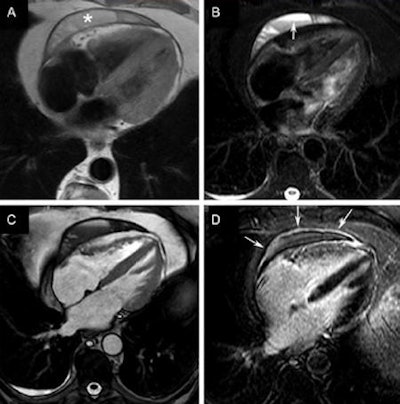

Cardiac MRI

MRI can visualize many RIHD-related pathologies, including epicardial coronary artery stenosis, microvasculature on myocardial perfusion, and ventricular function and viability, the authors noted. Stress myocardial perfusion can identify reversible myocardial ischemia, and CMR is the gold standard for myocardial assessment, and superior to SPECT for detecting hemodynamically significant stenosis. For myocardial edema in the setting of acute myocarditis, T2-weighted fast spin-echo imaging, using a short-tau inversion-recovery (STIR) sequence (triple inversion recovery), depicts increased free water in areas of high signal intensity.

Bright-blood cine CMR using balanced steady-state free precession (SSFP) gradient-echo sequences, provides dynamic information to quantify ventricular volumes, function, and mass; assess regional myocardial function; and visualize valvular heart disease. Myocardial deformation patterns can be evaluated using CMR tagging techniques. Another important CMR technique is velocity-encoded or phase-contrast cine CMR to measure the degree of dephasing caused by through-plane motion of protons. However, CMR suffers from limited availability in many centers and requires the use of contrast to detect coronary artery calcium.